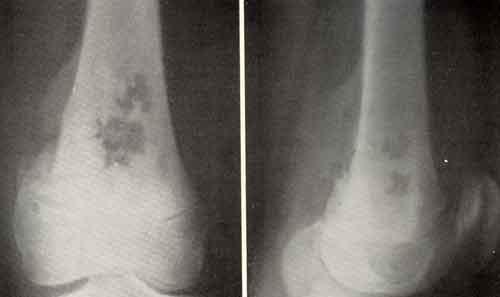

Остеогенная саркома – злокачественная опухоль, клетки которой развиваются из костной ткани. Данная опухоль чрезвычайно злокачественная и характеризуется бурным течением и ранним разрастанием метастазов. Рентгенологически саркома подразделяется на остеоплатсическую (склеротическую), остеолитическую и смешанную формы.

Остеогенная саркома может возникать в любом возрасте, но большинство случаев приходится на возраст от 10 до 30 лет, причем, мужчины болеют в 2 раза чаще женщин. Самая распространенная локализация опухоли в трубчатых костях нижних конечностей, реже поражаются плоские и короткие кости. Излюбленное место новообразования – коленный сустав, далее идет бедро, на долю которого приходится 50% всех сарком данного типа. Располагаться опухоль может также в большеберцовой, малоберцовой, локтевой, тазовой, плечевой кости. Череп поражается остеогенной саркомой преимущественно у детей или в старости, как осложнение остеодистрофии.

- Рентгенография, в частности с контрастным веществом.

Несмотря на такие прогрессивные методы диагностики саркому на начальных стадиях выявить практически невозможно. По одним только симптомам сложно судить о подлинности заболевания. При диагностике остеогенную саркому следует дифференцировать от хондросаркомы, хрящевого экзостоза, эозинофильной гранулемы, остеобластокластомы.